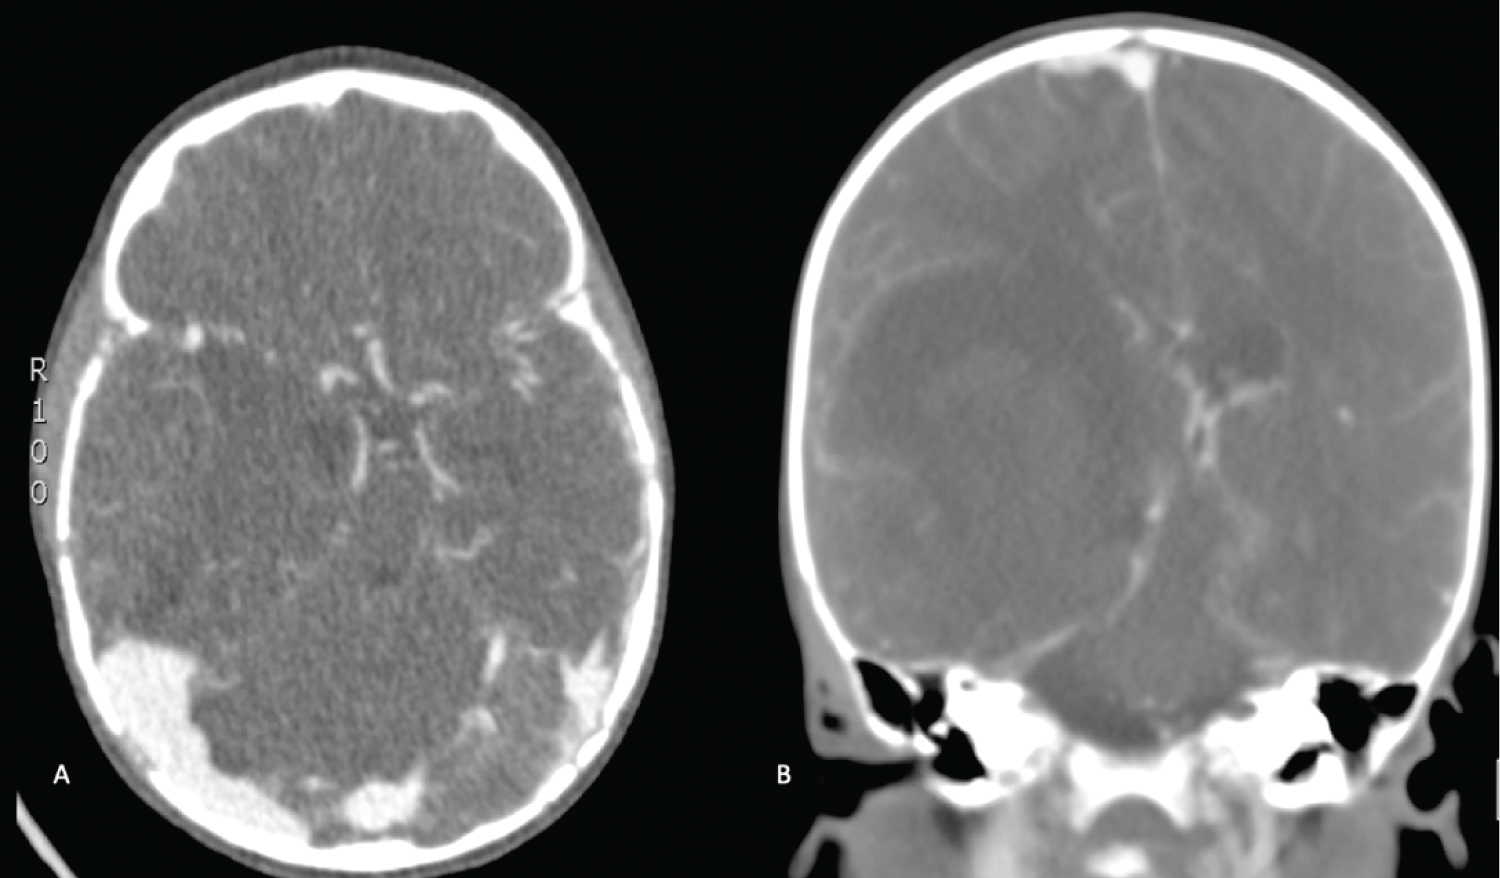

Given the history of HA, a computed tomography (CT) scan of the head was ordered, which demonstrated a 5.6 × 3.7 cm acute intraparenchymal hematoma (IPH) centered on the right basal ganglia with associated 12 mm of leftward midline shift and right uncal herniation (Figure 1). At this time, the patient was given 500 IU factor VIII (Advate), 10g mannitol (1 g/kg), and 200 mg levetiracetam (20 mg/kg). CT angiogram was negative for an underlying vascular malformation or aneurysm (Figure 2). Given the significant midline shift as well as uncal and subfalcine herniation, the patient was taken to the operating room emergently for a right-sided decompressive hemicraniectomy and evacuation of the hematoma.

Figure 2: A) Axial; B) Coronal. CT Angiography: Demonstrating a right basal ganglia centric intraparenchymal hemorrhage causing mass effect with a 12 mm midline shift, right uncal herniation. There is no definite arterial blush suggestive of active bleeding within the hematoma. No suggestion of underlying vascular malformation. View Figure 2